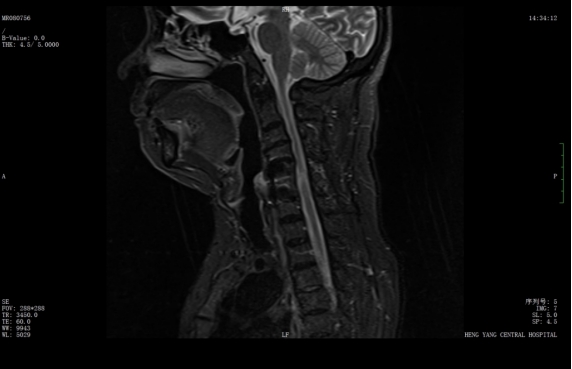

經(jīng)過(guò)精準(zhǔn)手術(shù)和術(shù)后系統(tǒng)的康復(fù)治療,患者神經(jīng)功能得到明顯恢復(fù),四肢肌力及感覺(jué)逐步改善,術(shù)后肌力達(dá)到IV級(jí)左右。復(fù)查X線(xiàn)顯示內(nèi)固定位置理想,患者非常滿(mǎn)意。出院之際,患者及家屬對(duì)衡陽(yáng)市中心醫(yī)院的醫(yī)療技術(shù)、護(hù)理服務(wù)及醫(yī)聯(lián)體轉(zhuǎn)診效率均給予高度評(píng)價(jià)。

術(shù)后x線(xiàn)內(nèi)固定位置理想